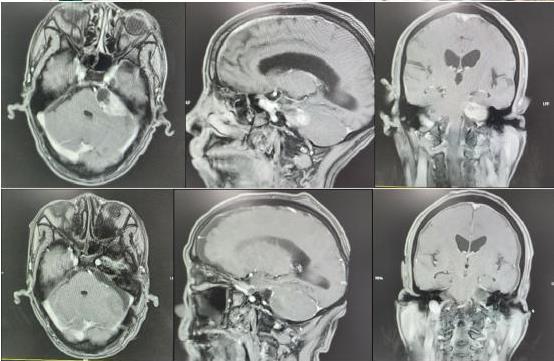

经查,排除了脑出血或脑梗,但核磁共振显示老王脑袋里长了一个鸡蛋大小的肿瘤,这让老王全家陷入了恐惧之中。

拿着各项检查结果,老王及家人找到在第一师医院神经外科开展援疆工作的赵明飞副主任(来自浙江大学医学院附属第二医院),经过询问病史和阅片,赵明飞告诉患者及家属,老王的听力障碍及面部麻木等症状可能是脑袋里的这个肿瘤引起的,专业术语叫“听神经鞘瘤”,且大小约3*4cm,属于四级听神经鞘瘤,脑干、小脑已经明显受压移位,需尽快手术治疗,不然后期可能会导致肢体功能障碍、昏迷、甚至危及生命。

手术在全麻下进行,术中,赵明飞发现肿瘤充满桥小脑角,与岩静脉、三叉神经等黏连紧密,他带领刘俊医生在显微镜下仔细分离黏连,逐步切除肿瘤,同时应用神经电生理监测技术,仔细分离保护面神经,历经4小时,最终将肿瘤完整切除,正常血管神经完好保留。